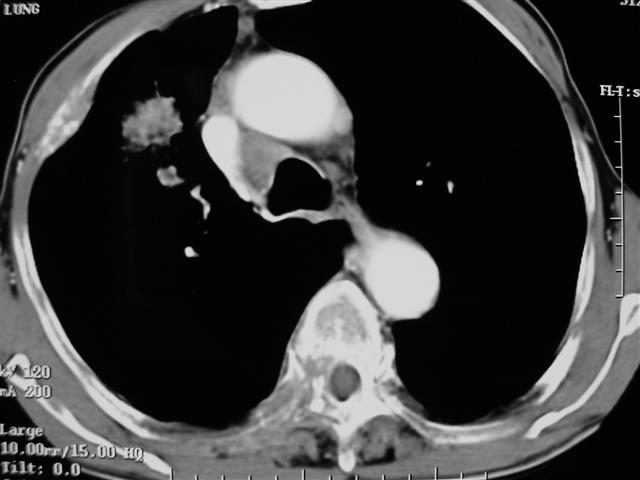

男,64岁,咳嗽、咳痰20余天,明显消瘦,x线片发现肺部阴影

长毛刺、肺门引流征象、中心液化坏死等应该是提示结核性肿块的可能性大,但是合并椎体及多处肋骨破坏则周围型肺ca并椎体及多处肋骨转移不能除外。

1)右肺上叶前段周围型肺癌并阻塞性肺炎、右肺门及纵隔淋巴结转移、肋骨及胸椎转移。2)右肺上叶后段纤维病灶。